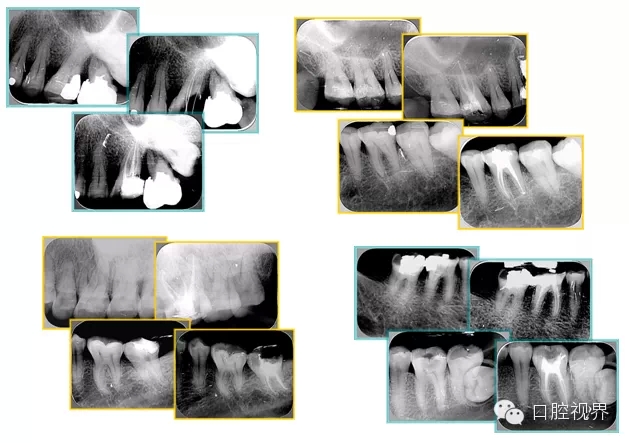

2. X 線片

共有 4 張 X 線片,分別是術(shù)前、診斷絲 、主牙膠尖確認(rèn)、術(shù)后。

( 1 )術(shù)前:術(shù)前 X 線片用來了解牙齒的大概情況。術(shù)前預(yù)期為多根牙時 X 線片應(yīng)偏頭拍攝。

( 2 )診斷絲:根據(jù)術(shù)前 X 線片進(jìn)行開髓、根管的初步預(yù)備后,需要插入診斷絲,用來指示工作器械位置。常用 10 號或 15 號擴(kuò)大器作為診斷絲插入牙髓腔。

( 3 )主牙膠尖確認(rèn):通過術(shù)前預(yù)期和診斷絲診斷,明確工作長度、牙根走向,進(jìn)行根管預(yù)備。之后應(yīng)進(jìn)行主牙膠尖(中銼)確認(rèn),已明確根管是否適合充填。

( 4 )術(shù)后:觀察治療效果。